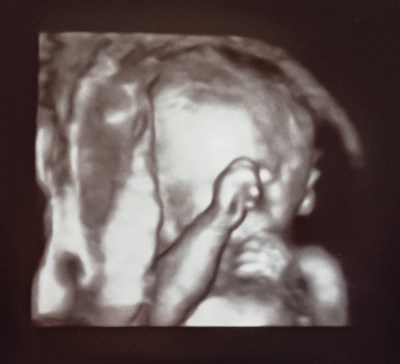

Ultrasound #4

Two weeks later, I was back at my clinic for another ultrasound. My doctor wanted a better picture of Hobbit’s face, and, as noted earlier, I was more than happy to oblige. Since I thought this would be a quick appointment and because I’m hoarding my sick time to apply towards my totally unpaid maternity leave (thanks, America), Matt and I decided we’d just make this appointment for whenever I could go and we wouldn’t worry about Matt’s schedule. He’d made it to the Big One, and we thought this one would just be supplementary.

Happily for me, this appointment’s ultrasound tech told me she’d just been looking at “plain old uteruses” all day, and did I mind if she took more pictures than we really needed to? Ummmmm, hell no! I said (with my eyes). On this day, Hobbit cooperated fully, and the pictures we got out of this visit absolutely knocked the wind out of me.

I was pretty much over the moon and could not wait to show Matt the new prints.

And now, for the 3D shots! I must admit that when I’ve seen these in the past, I was both amazed and a little weirded out by just how detailed they can be, but now that it’s our kid, I am only 1,000% amazed.

![]() |

| Sleepy baby (with a huge tricep). |

| So shy. |

| And, our favorite: two little fists tucked under his chin. |

Can you believe it? There he is! Our son. Our son. Oursonoursonoursonoursonourson.